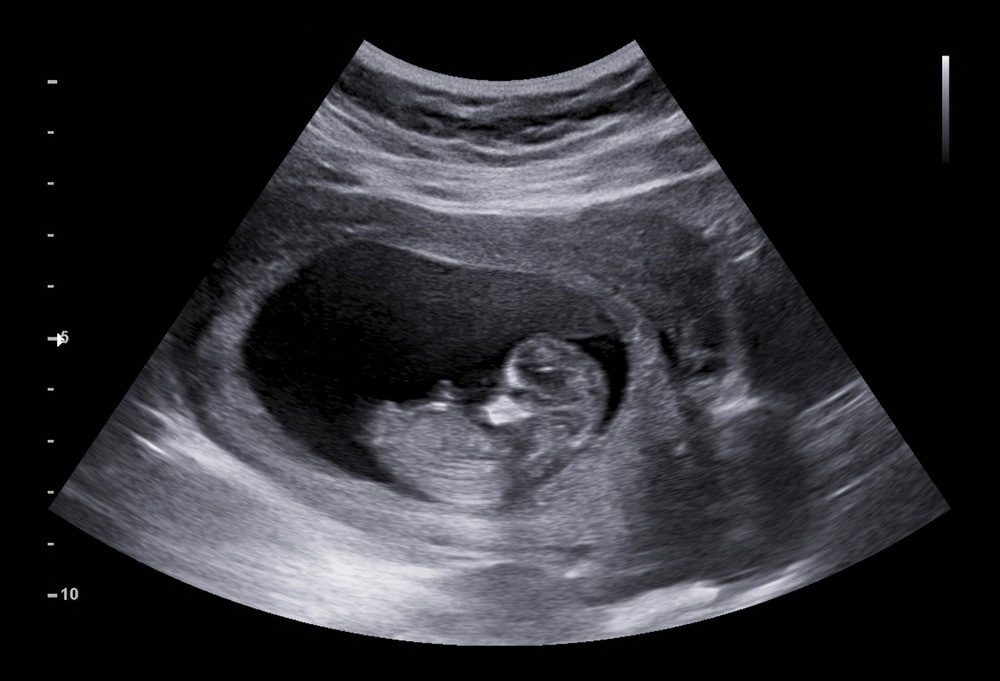

Fetus

Image Credit: AePatt Journey/Shutterstock.com